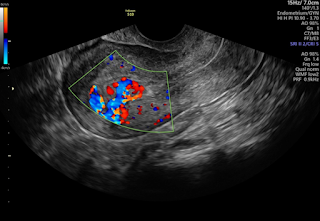

A pelvic ultrasound is one of the most effective and non-invasive methods to evaluate adenomyosis. It helps detect:

• Thickened uterine walls

• Enlarged uterus

• Heterogeneous myometrium

• Other associated conditions like fibroids